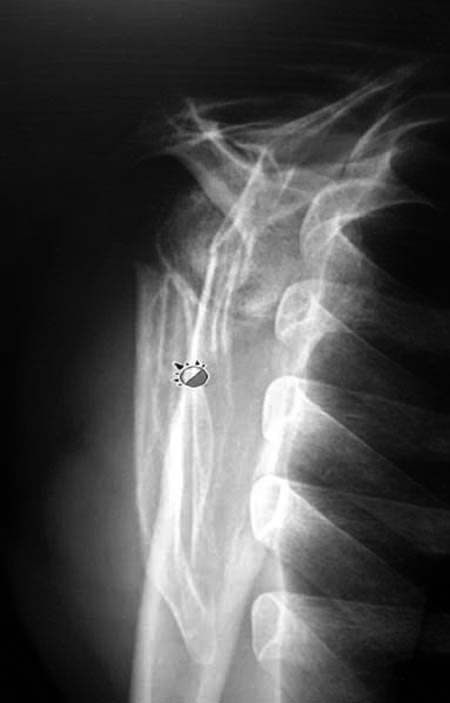

Данный перелом относится к перелому тело лопатки и несмотря на наслоение, где лопатка покрывает грудную клетку, но можно увидеть три большие фрагмента, которые находятся в разных плоскостях. Суставная поверхность расположена намного медиальнее, что нарушает бланс мышц, которая в последующем может привести к ограничению движения верхного пояса. Расположение суставной поверхности нуждается в уточнении дополнительными исследованиями, включая КТ и стандартные снимки плеча.!

Здесь пример, стандартные снимки: плечо и лопатка прямой снимок, аксиллярный и косой снимки (Y-view) и фиксация пластинами по краям, где имеется более твердая кость. Специальные пластины, хотя любая 2.7 или 3.5 мм тубулярная пластина подойдут для фиксации перелома. Риск операции - это повреждение нерва во время доступа и ре-фиксация ротаторной манжетки если потребуется широкий доступ!